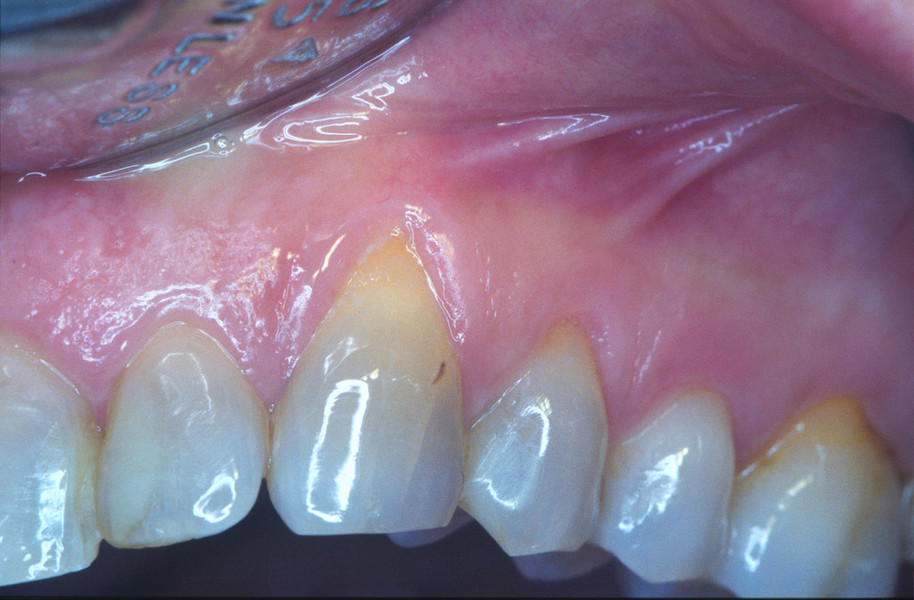

LA CHIRURGIA MUCOGENGIVALE

E ' QUELL'INSIEME DI TECNICHE CHIRURGICHE TESE AD APPORTARE DEI CAMBIAMENTI NELLA ARCHITETTURA DEI TESSUTI MOLLI, PER  OTTENERE UNA STABILIZZAZIONE DEGLI STESSI AI FINI, SIA ESTETICI, SIA  DELLA PRESERVAZIONE DELLA STABILITA' DEGLI ELEMENTI DENTARI.

UNA DELLE TECNICHE DI INNSTO LIBERO